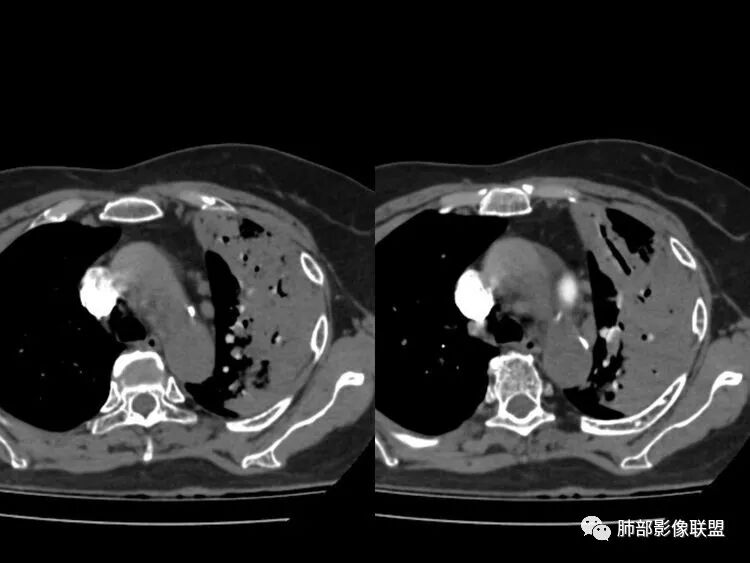

经痰涂片及CTPA检查的结果:肺结核合并肺栓塞。

影像特点支持结核。气促、左上肺病灶似乎不能解释I型呼吸衰竭加上D—二聚体明显升高、肺动脉干增粗,临床需要想到二元可能:肺结核合并肺栓塞可能,需要完善CTPA明确有没有肺栓塞,因为急性肺栓塞是急危重症。

1.老年女性,胸闷、气促半个月入院。无发热、咯血、胸痛等。

既往糖尿病病史。双下肢凹陷性水肿。

降钙素高,D-二聚体升高,结核感染T细胞检测阳性。呼衰。

1.左肺上叶较大范围实性密度区,支气管未见阻塞,无壁空洞,整体比较“干”,加之纵隔左移,比较符合病程较长的结核性病变。

左肺下叶多发结节影、条索影、树芽征等具有相当明显的提示意义—符合继发性肺结核。

2.“胸闷、气促”以及呼衰的临床表现,难以以当前肺部的病灶加以解释。

D-二聚体升高,肺动脉成像等明确患者肺栓塞的存在!